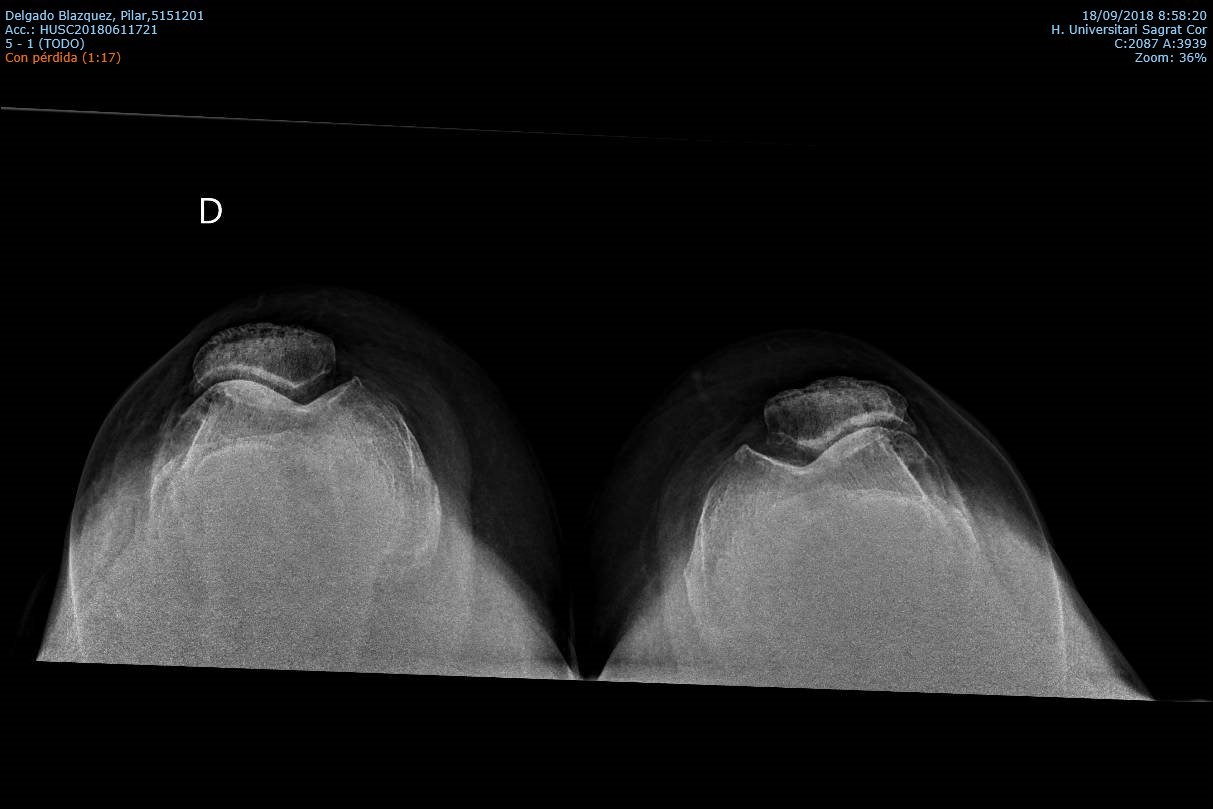

Diagnostico

Los estudios previos para el diagnostico de una artrosis de rodilla son principalmente un examen clínico del médico y las radiografías. El examen medico habitualmente confirma dolor en la parte medial, anterior y lateral de rodilla, rigidez con reducción en el rango de movimiento, crepitación o roce con el movimiento de la rodilla y cojera durante la marcha. En la radiografía típicamente se observa los cambios en la forma del hueso y cartílago como la pérdida de grosor, deformación y endurecimiento. Ocasionalmente para confirmar el diagnóstico de la patología de un compartimiento o de una fase muy inicial, se puede usar otras pruebas de imagen como la resonancia magnética, tomografía computarizada (TC) o gammagrafía ósea que valora mejor las partes blandas alrededor de la articulación.

La Prótesis Femoropatelar de Rodilla.

La prótesis parcial femoropatelar de la rodilla es una prótesis especial que está indicado en pacientes con un desgaste muy inicial y con un patrón que afecta solo el compartimiento anterior de la rodilla. Típicamente, son pacientes con dolor en la parte de delante de la rodilla al estar sentados o al subir o bajar escaleras. No les molesta al caminar sobre un terreno plano sin desnivel. Tiene la ventaja de resecar mucho menos hueso del paciente, así preservando más hueso para el futuro. Además, al mantener la parte biológica del cartílago y la ligamentosa de los cruzados de la rodilla, parece conservar mucho mejor la sensibilidad y la marcha de la rodilla (la propiocepción). También la recuperación de esta cirugía (al ser menos agresiva) es más rápida.

|

|

Los mejores resultados de supervivencia se ven en pacientes con poca enfermedad y poca deformidad del aparato extensor, mayor de edad o con normo/bajo peso. Los pacientes candidatos a esta protesis probablemente no son más de 2-3 % del total de pacientes con artrosis de la rodilla. Además, su uso es restringido debido a la probabilidad de la progresión de a enfermedad dentro del resto de la articulación, que puede ser generador del dolor y fracaso de la prótesis con el paso de los años. Por tanto, cuando se decide por optar por este implante precisa un consenso claro entre el cirujano y el paciente entendiendo todos los variables que puedan surgir. Siempre que se plantea colocar una protesis femoropatelar habitualmente también se tiene preparado la protesis total por si el grado de enfermedad comprobado durante la cirugía es más de la prevista antes de la cirugía.